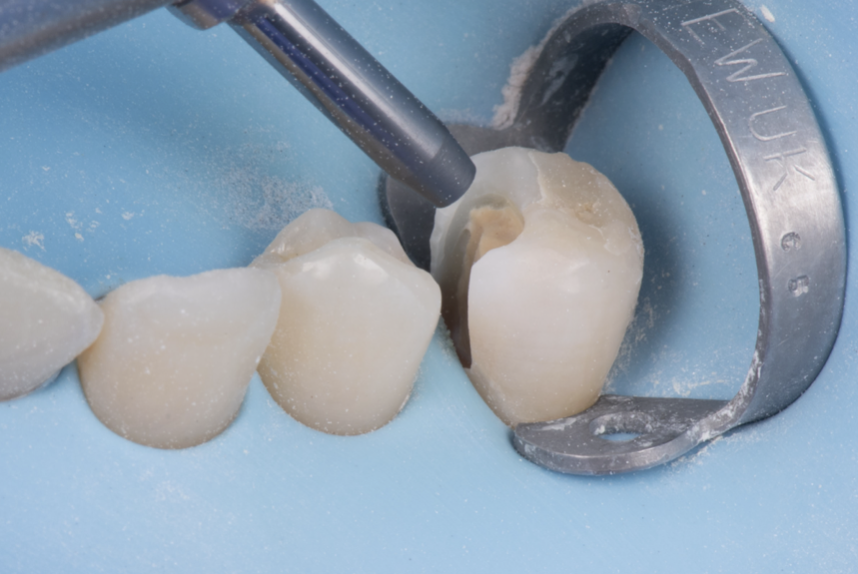

• Rubberdam plaatsing bij diepe laesies;

• Toepassing van pulpa-afdekmaterialen;

De cursus bestaat uit een combinatie van interactieve theorie en praktische oefeningen. Er wordt gewerkt met preparatiemodellen waarin een diepe caviteit en pulpablootstelling wordt gesimuleerd.

• Preparatie van diepe caviteiten in molaren;